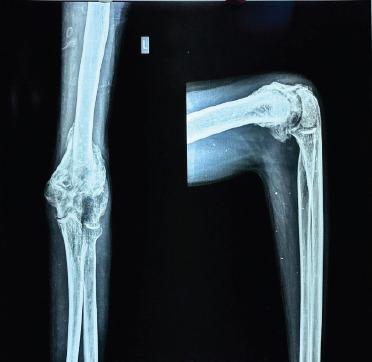

A 31-year-old man presented to the OPD 5 months after injury following 3 cycles of native splinting for distal humerus fracture. He had severe painful restriction of movements, with diffuse tenderness and deformity over the elbow joint affecting his ADL. He underwent a left elbow manipulation under anaesthesia after capsular release.

The clinical decision of choosing open approach versus arthroscopic approach is determined by the severity of the stiffness. In our case, since the patient has severe stiffness with only 30° arc of motion, we decided to go ahead with an open arthrolysis and the patient had good functional improvement.

一名31岁男性在因肱骨远端骨折接受3个周期的传统夹板固定治疗5个月后到门诊就诊。他的肘关节活动严重受限且疼痛,关节弥漫性压痛和畸形,影响了他的日常生活活动。在进行关节囊松解后,他接受了左肘关节麻醉下手法松解。

选择开放手术还是关节镜手术的临床决策取决于僵硬的严重程度。在我们的病例中,由于患者僵硬严重,活动弧度仅为30°,我们决定进行开放性关节松解术,患者的功能得到了良好改善。